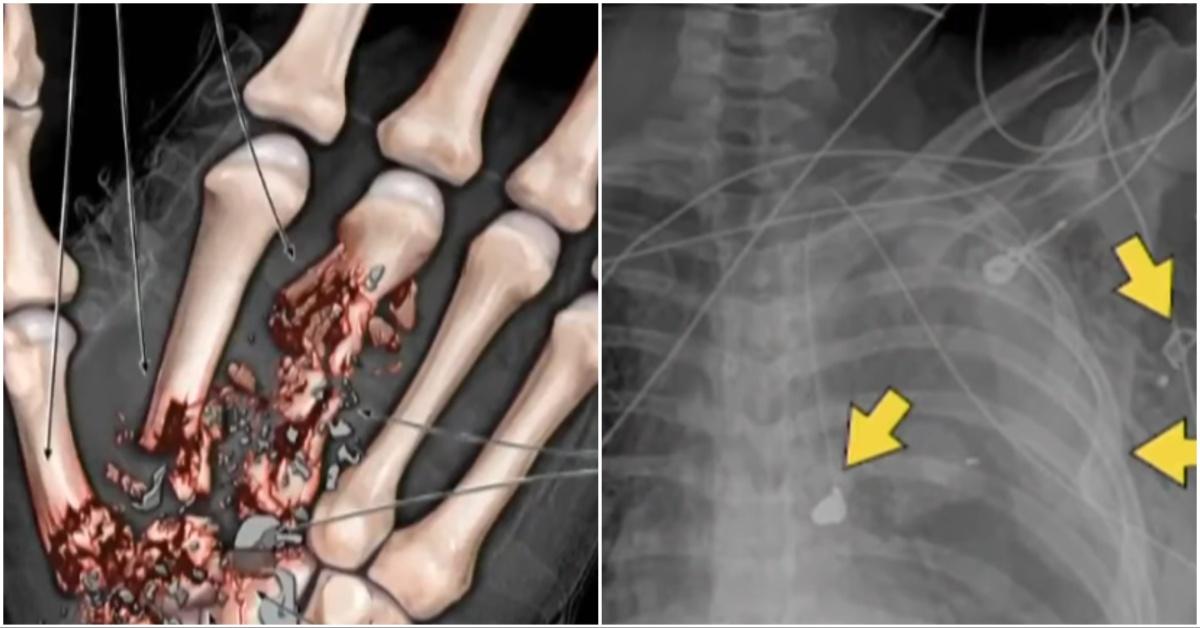

On the day of the shooting, Abigail Zwerner was sitting at a reading table in her first-grade classroom when a single shot rang out. The bullet passed through her hand and into her chest. She managed to escort her students to safety before collapsing in the school office.

Abigail Zwerner spent nearly two weeks in the hospital, underwent six surgeries, and still does not have full use of her left hand. During her testimony in court, she recalled thinking, “I thought I was either on my way to heaven or in heaven … then it all got black.”